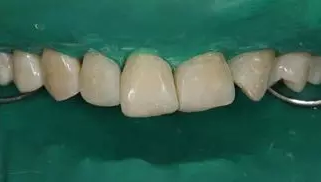

5.牙體微預備:放置橡皮障,再次確認硅橡膠背板就位良好后,11,12,21,23 使用金剛砂車針輕輕打磨一層厚度約 0.1mm,切忌對整個唇面進行打磨。

病例分享|復合樹脂微創(chuàng)美學修復關閉上前牙間隙

牙體微預備

8.分層堆塑:硅橡膠背板就位于口內,使用瓷納美E2 色樹脂進行腭側堆塑,形成厚約為 0.5mm 腭側釉質壁,光照20s,移走硅橡膠背板,腭側繼續(xù)光照 20s。接著使用 D2 色樹脂進行充填,注意充填的厚度約為0.5mm,長度短于切端1~2mm,且頸部的厚度應逐步遞減。然后使用 E2色樹脂恢復唇面及切端,厚度約為1~1.5mm。堆塑時應兩顆牙同時進行,以便及時調整牙齒的寬度,堆塑完成后應檢查兩牙寬度是否一致,是否協(xié)調對稱,有無懸突等。

E2樹脂堆塑腭側釉質壁

移除硅橡膠導板后

D1 色,E2色分層堆塑完成